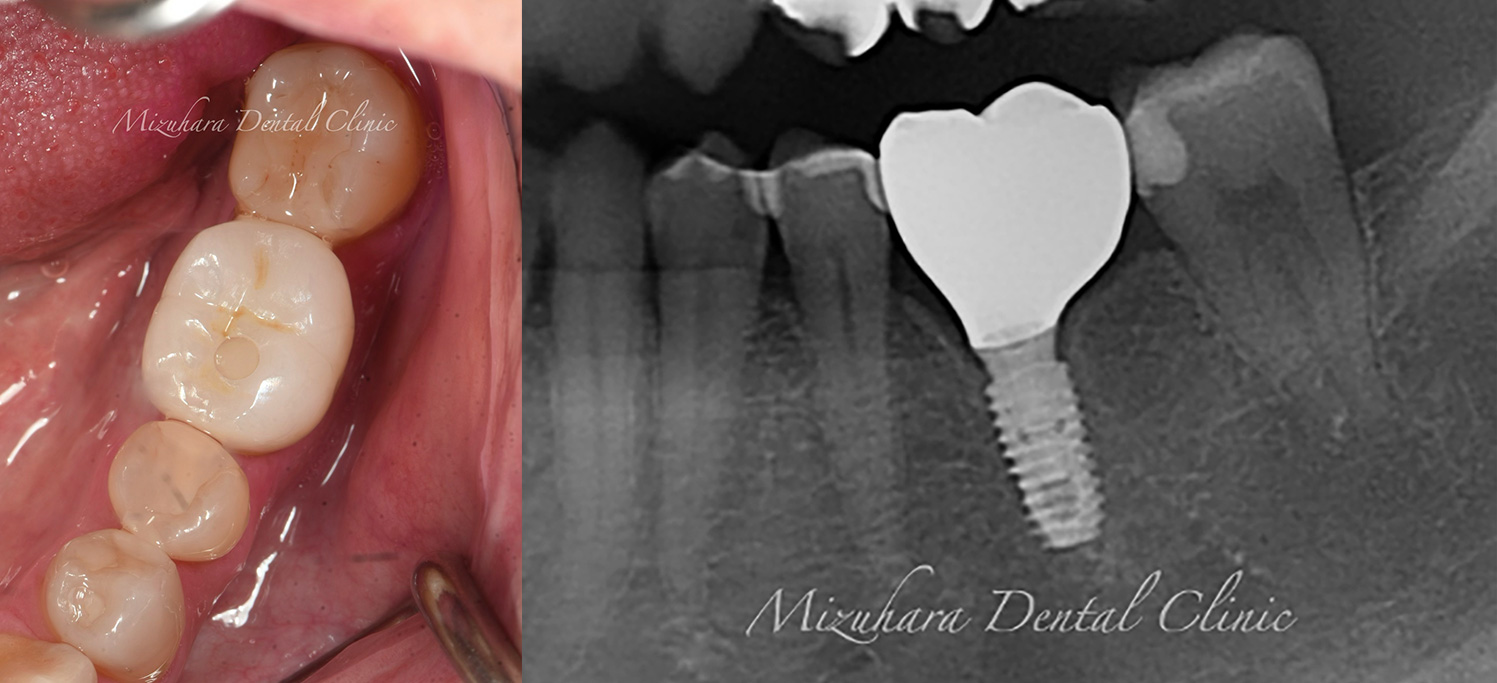

豊富な臨床経験に基づくインプラント治療

インプラント治療

米インディアナ大学歯学部 インプラント科のプログラムを受講し、国際的な教育環境のもとで臨床経験を積んだ当院長によるインプラント治療。

CASE

症例紹介

三鷹の歯医者【みずはら歯科・矯正歯科 三鷹】